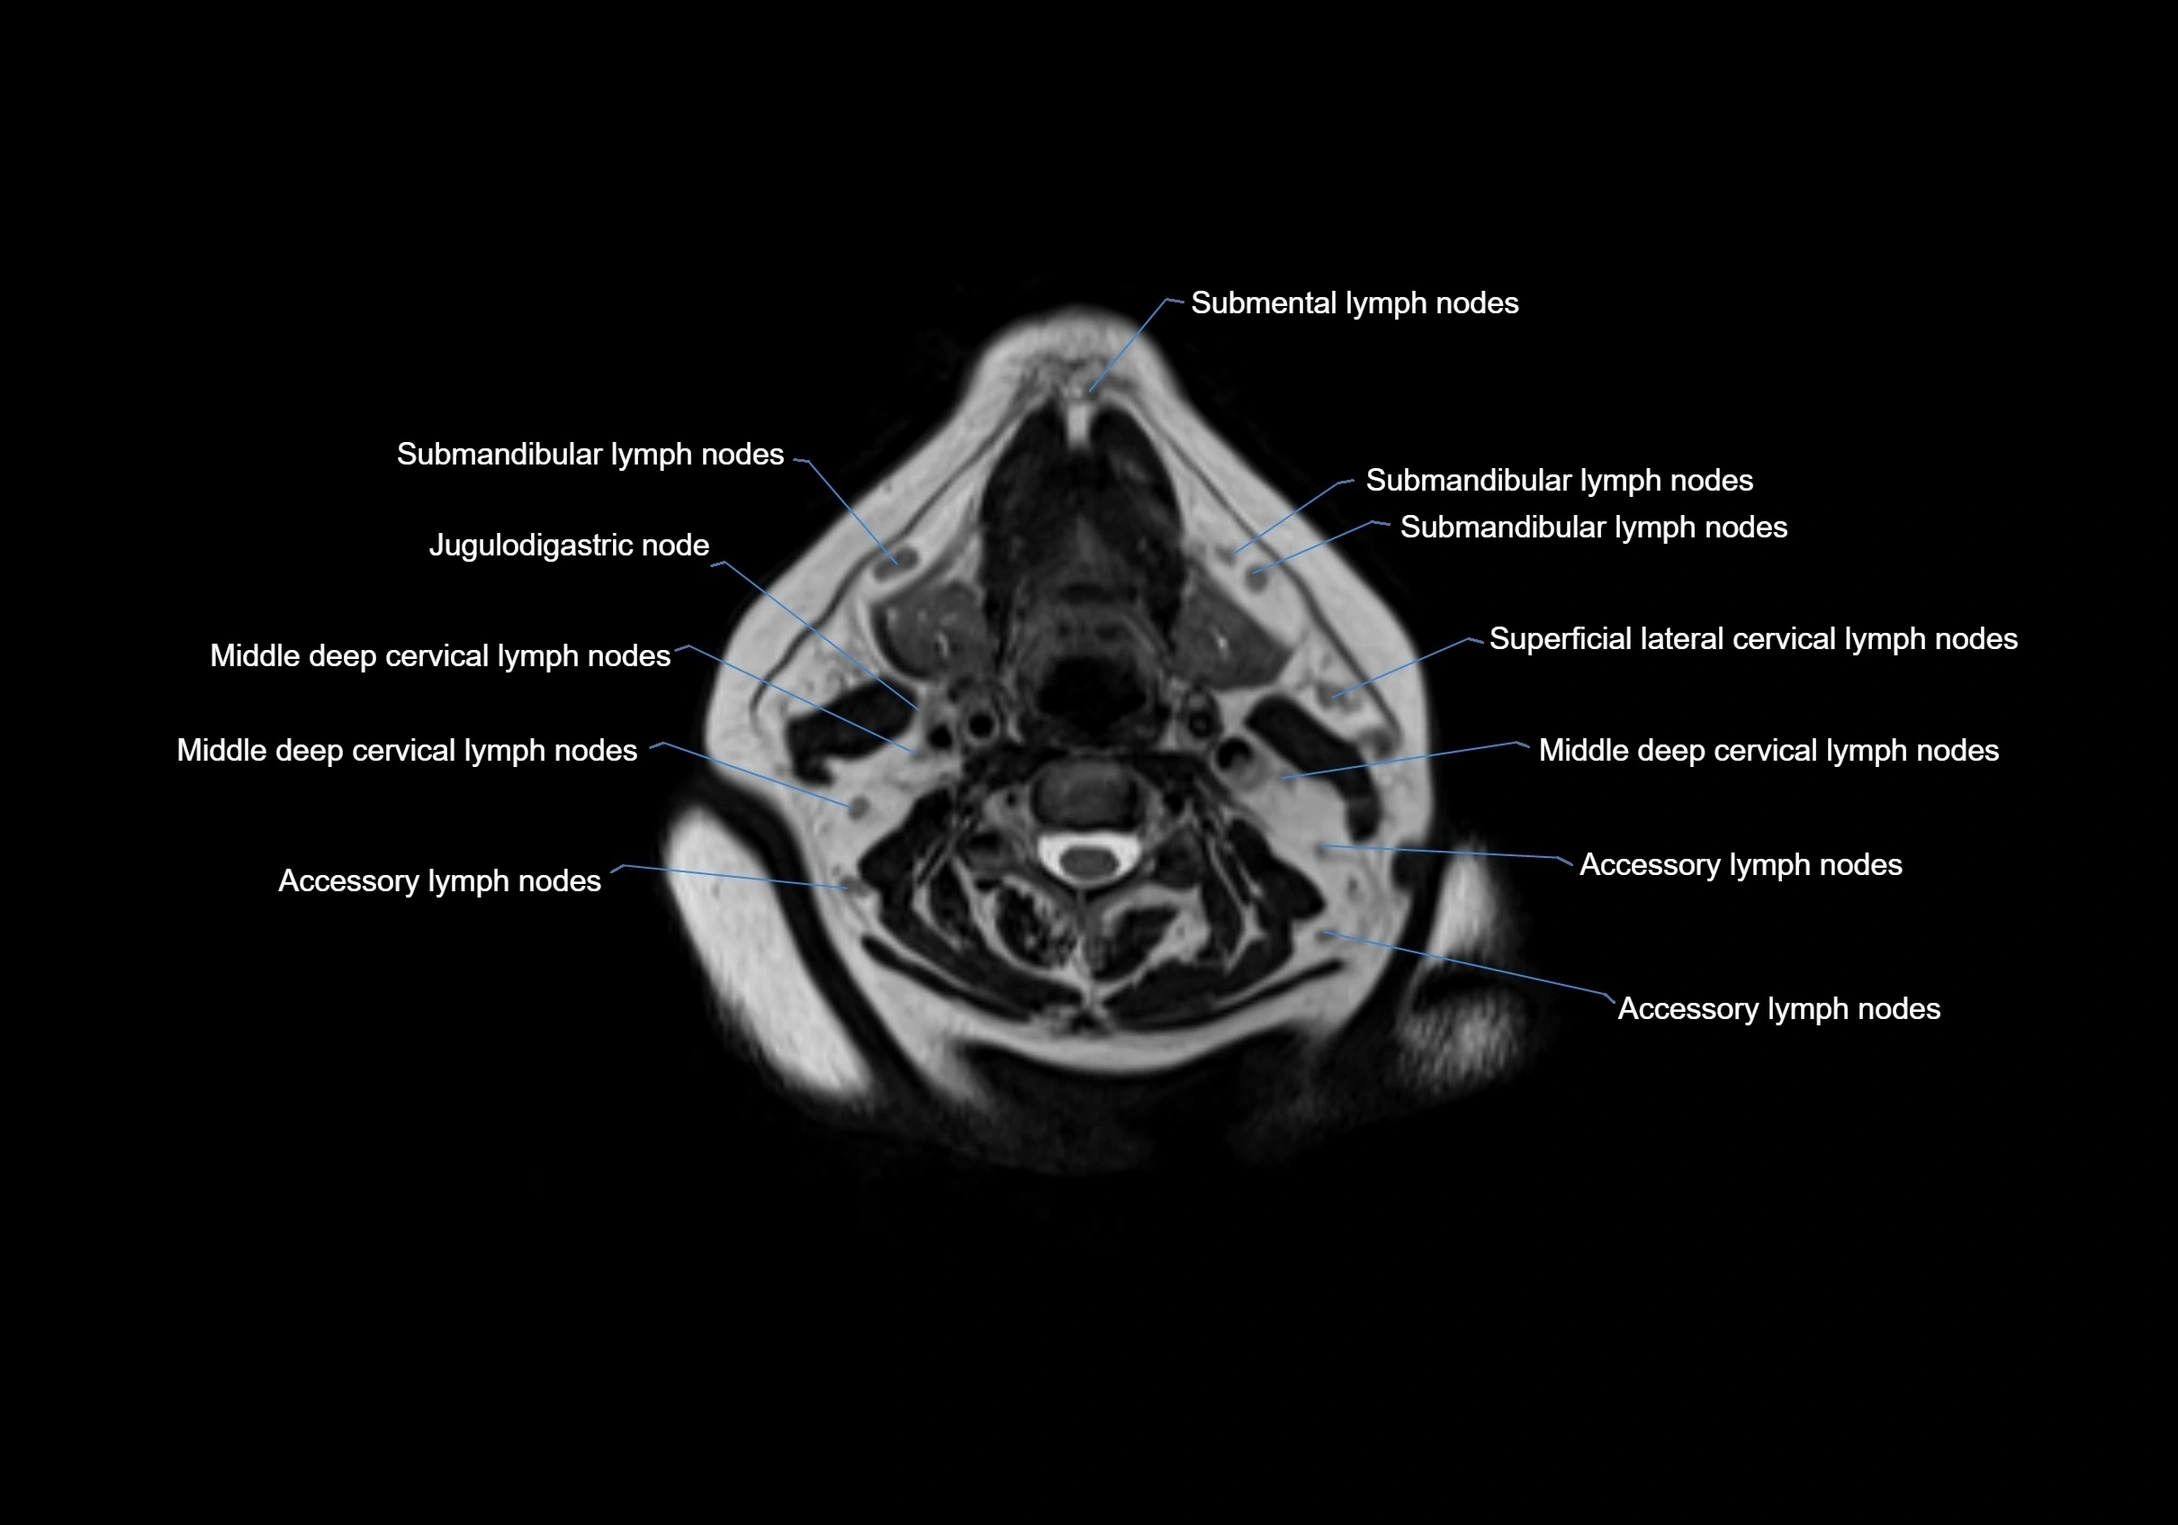

Accessory lymph nodes

Accessory lymph nodes are small, secondary lymph nodes located along the main facial and cervical lymphatic chains, often adjacent to primary lymph nodes, such as preauricular, submandibular, or occipital nodes. They are typically less than 5 mm in diameter, embedded within subcutaneous fat or connective tissue, and may be variable in number and location. These nodes provide additional filtration and immune surveillance for lymph collected from the face, scalp, and neck regions. Accessory lymph nodes are usually non-palpable in healthy individuals but may enlarge in response to infection, inflammation, or metastasis, making them clinically significant.

• Found along primary lymph node chains, including preauricular, submandibular, parotid, and occipital regions

• Embedded in subcutaneous fat or superficial fascia, often lateral or posterior to primary nodes

• Variable in number; may occur unilaterally or bilaterally, depending on individual anatomy

MRI Appearance

T1-weighted images:

• Normal accessory nodes appear as small, oval hypointense to intermediate signal structures within subcutaneous fat

• Surrounded by hyperintense fat, enhancing contrast for visualization

• Pathological nodes may appear enlarged or rounded, sometimes with cortical thickening

MRI images

image